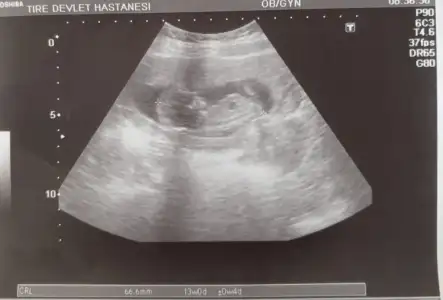

Bizim bacak arasına baktı dedi ki pipi göremiyorum ama birkaç haftaya netleşirBizim ikili testte de ense kalınlığı 1 mm çıktı çok şükür. 12+6 dedi. Normalde 12+2 diye biliyordum. Cinsiyet erken dedi bana da